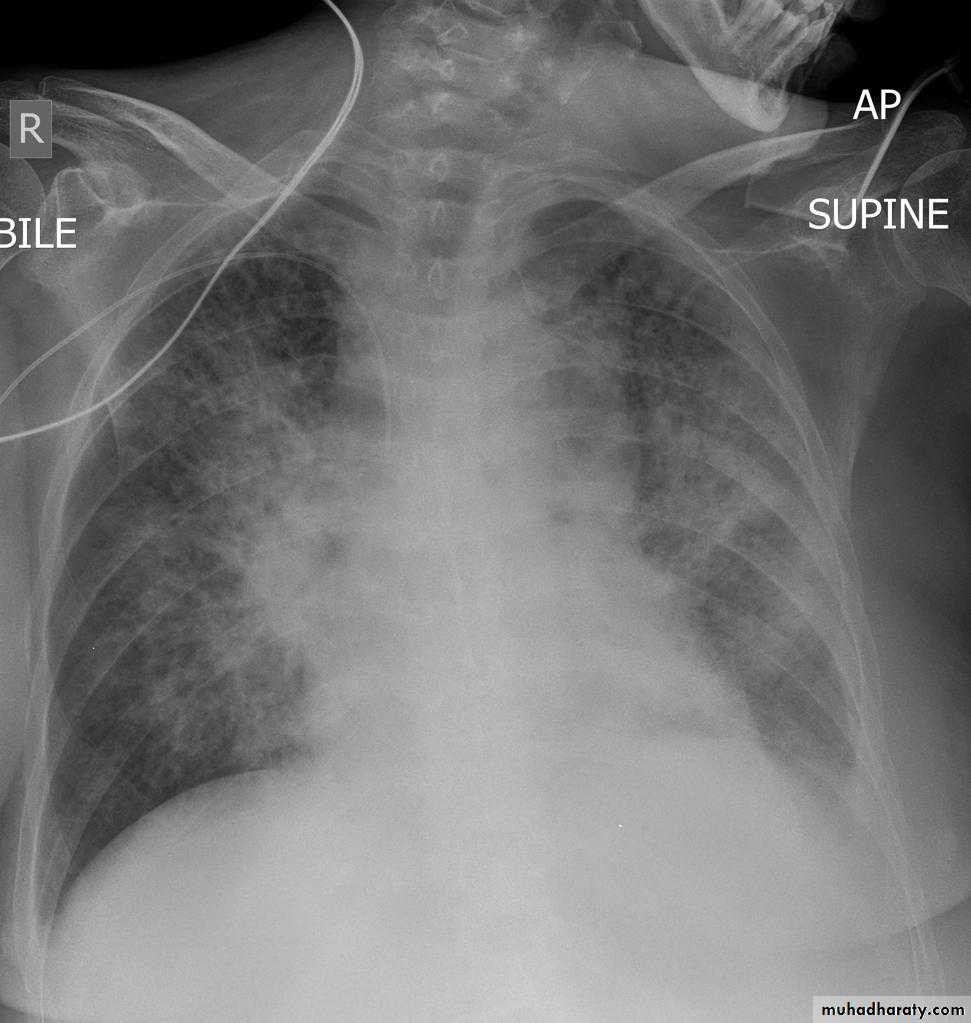

Interstitial pulmonary edemaCXR of adult , PA view shows:Bilatral patchy opacity involving mainly lower lung fields with enlargement of cardiac shadow